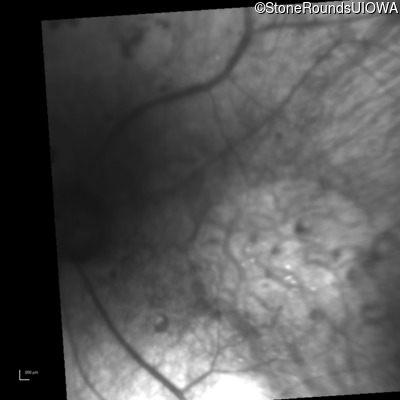

Infrared Fundus Photograph - Right - Hand Motion 1' sc

Exemplar